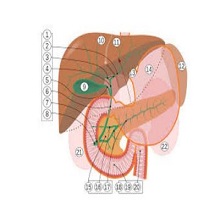

| Цироза јетре је хронична болест код које оштећење ћелија јетре изазива инфламацију, некрозу и активацију звездастих ћелија што доводи до инсуфицијенције јетре и / или малигног тумора. |

Ултразвучни преглед јетре је неинвазивна, брза, једноставна , дoступна и поуздана дијагностичка процедура која се користи за процену величине, структуре и стања јетре и представља први корак у дијагностици обољења јетре. |

Вилсонова болест је генетски аутозомно рецесивни поремећај у коме се бакар ексцесивно накупља у јетри и мозгу. |

| Жучни канали су склони зачепљењима и упалама, а то су, поред појаве камења, и неки од највећих проблема у раду жучне кесе. |

| Акутни холециститис је акутно запаљење зида жучне кесице праћено болом у трбуху под десним ребарним луком. Чести симптоми су још и повишена телесна температура, мучнина и повраћање. У око 90% случајева удружено је са билијарном калкулозом (камен у жучној кесици). Акутни холециститис се најчешће јавља као акутна егзацербација хроничног холециститиса. |